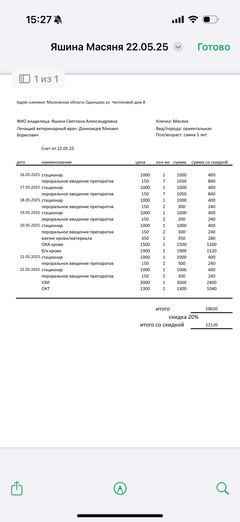

Ярко выраженная болезненность в области крестца, на обезболе полегче. По результатам приема невролога проведена миелография - множественная компрессия, возможно опухоль, возможно грыжа, нужно удалять...

Баланс на 12.06.2025: минус 32 396,34